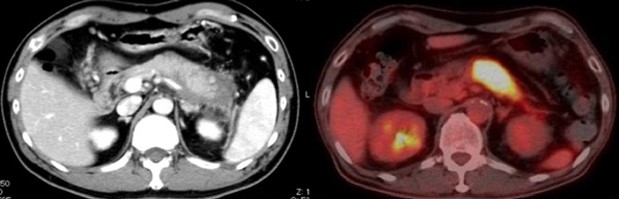

自己免疫性膵炎は高齢男性によく発症する指定難病で、膵臓が大きく腫れて黄疸・腹痛を伴い、悪化と治癒を繰り返すことが特徴です。この自己免疫性膵炎は、IgG4という特殊な抗体を作る免疫細胞が膵臓に集まることで発症するIgG4関連疾患であることが知られています。

まず、マウスにpoly(I:C)※8を反復投与し、自己免疫性膵炎モデルマウスを作成しました。モデルマウスを用いて検証を行った結果、発症初期には膵臓に炎症の原因とされる形質細胞様樹状細胞はほとんど存在せず、活性化された通常型樹状細胞がサイトカインであるI型IFNとケモカインであるCXCL9・CXCL10※9を産生し、初期の炎症を誘導することが明らかになりました。次に、CXCL9・CXCL10に反応してCXCR3陽性CD4T細胞が膵臓に誘導され、この細胞がさらなる炎症をもたらすことがわかりました。また、CXCR3陽性CD4T細胞はインターフェロン-γ※10を産生し、膵臓にダメージを与える一方で、ケモカインCCL25※11を膵臓で産生します。このCCL25が、最も炎症に大きな影響を与える形質細胞様樹状細胞を最終的に膵臓に引き寄せ、炎症が完成することが明らかになりました。つまり、通常型樹状細胞とCXCR3陽性CD4T細胞が初期の炎症を誘導し、CXCR3陽性CD4T細胞と形質細胞用樹状細胞が炎症を完成させることがわかりました(図)。さらに、完成期には形質細胞様樹状細胞とCXCR3陽性CD4T細胞が相互に活性化しあい、大量のI型IFN・CXCL9・CXCL10・CCL25が放出され、炎症が加速することも突き止めました。また、実際にTLR3・CXCR3・CCL25・I型IFNを阻害すると、炎症はほとんど起こりませんでした。ここから、通常型樹状細胞・形質細胞様樹状細胞・CXCR3陽性CD4T細胞を自己免疫性膵炎・IgG4関連疾患の病的細胞と同定し、病気の初期・完成期におけるこれらの細胞の役割をサイトカイン・ケモカインのレベルで明確にすることができました。